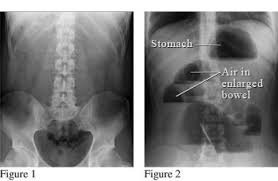

Plain Abdominal X Ray The V P Shunt Catheter Inside The Abdominal Cavity Download Scientific Diagram

X Ray Of Patient Shows The Tip Of The Abdominal Catheter Protruding Download Scientific Diagram

Ventriculoperitoneal Shunt Radiology Reference Article Radiopaedia Org

Ap and lateral abdomen ap and lateral chest ap and lateral c spine ap and lateral skull.

Vp shunt x ray positioning. The shunt series is a set of radiographic images performed to assess the location and integrity of a ventriculoperitoneal shunt. In the context of hydrocephalus there are a multitude of therapeutic options that can be explored in order to improve patient outcomes. The external portion of the catheter is connected to a valve that regulates the flow of csf based on a preset pressure.